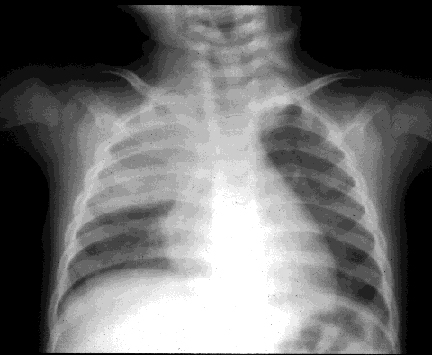

Initial chest x-ray

After examining the chest x-rays, the radiologist reported a right, upper lobe infiltrate.

The infiltrate is the hazy area in the upper right quadrant.